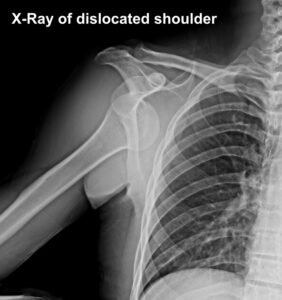

The shoulder joint is a ball and socket type of joint between the head of humerus (ball) and glenoid (socket). Shoulder dislocation is when the head of humerus (ball) completely pops out of the cup-shaped socket (glenoid). If it happens partially it is called subluxation.